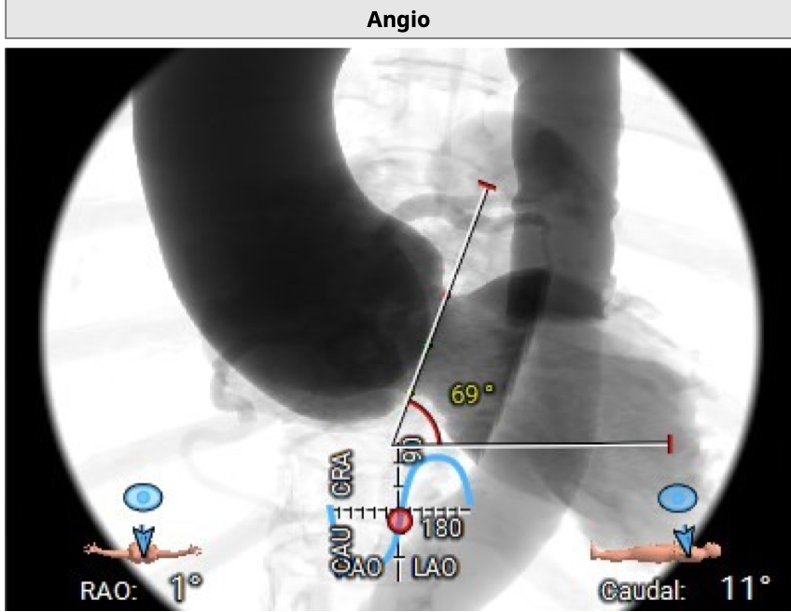

CT分析

双侧冠脉开口高度可LCA:13.9mm,RCA:21.8mm:

横位心: